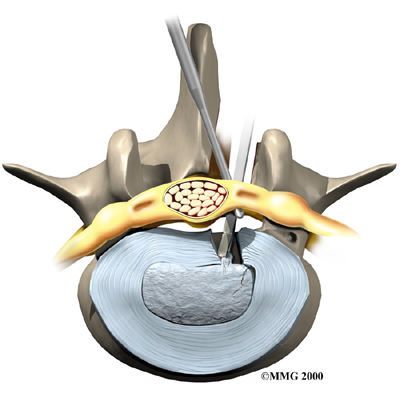

Microdiscectomy

Microdiscectomy is becoming the standard surgery for lumbar disc herniation. The procedure is used when a herniated disc is putting pressure on a nerve root. It involves carefully taking out part of the problem disc (discectomy). By performing the operation with a surgical microscope, the surgeon only needs to make a very small incision in the low back. Categorized as minimally invasive surgery, this surgery is thought to be less taxing on patients. Advocates also believe that this type of surgery is easier to perform, that it prevents scarring around the nerves and joints, and that it helps patients recover more quickly.

Related Document: FYZICAL Mandarin's Guide to Lumbar Discectomy